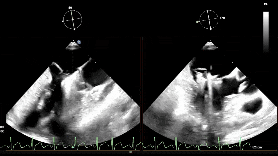

术中影像

房间隔穿刺

置入瓣膜夹

第一次关闭瓣膜夹

超声提示仍存在少量反流